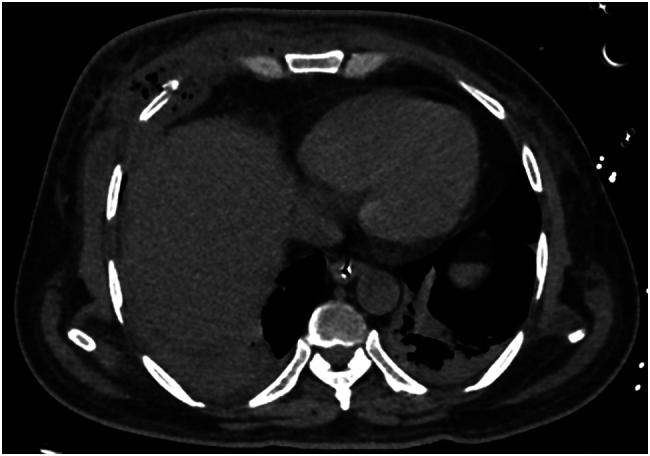

Blunt Trauma Chest (BTC) is a common cause of morbidity and mortality in trauma patients. Although rib fractures, haemothorax, pneumothorax and lung contusions are often found in tandem in BTC, delayed necrotising soft tissue infection (NSTI) without any penetrating injuries or overt puncture wounds have rarely been reported. We report a 61-year-old patient with uncontrolled diabetes, admitted after a motor vehicle collision with head, chest and lower limb injuries and discharged after 9 days of stay in the hospital. He returned with NSTI of the chest wall around a week later with a fulminant clinical course ultimately leading to septic shock, multi-organ dysfunction and demise of the patient.

钝性胸部创伤(BTC)是创伤患者发病和死亡的常见原因。虽然在BTC中经常同时发现肋骨骨折、血胸、气胸和肺挫伤,但很少有关于无任何穿透伤或明显穿刺伤的延迟性坏死性软组织感染(NSTI)的报道。我们报告一名61岁患有未控制糖尿病的患者,在机动车碰撞致头部、胸部和下肢受伤后入院,住院9天后出院。大约一周后,他因胸壁NSTI再次入院,临床过程迅猛,最终导致感染性休克、多器官功能障碍和患者死亡。